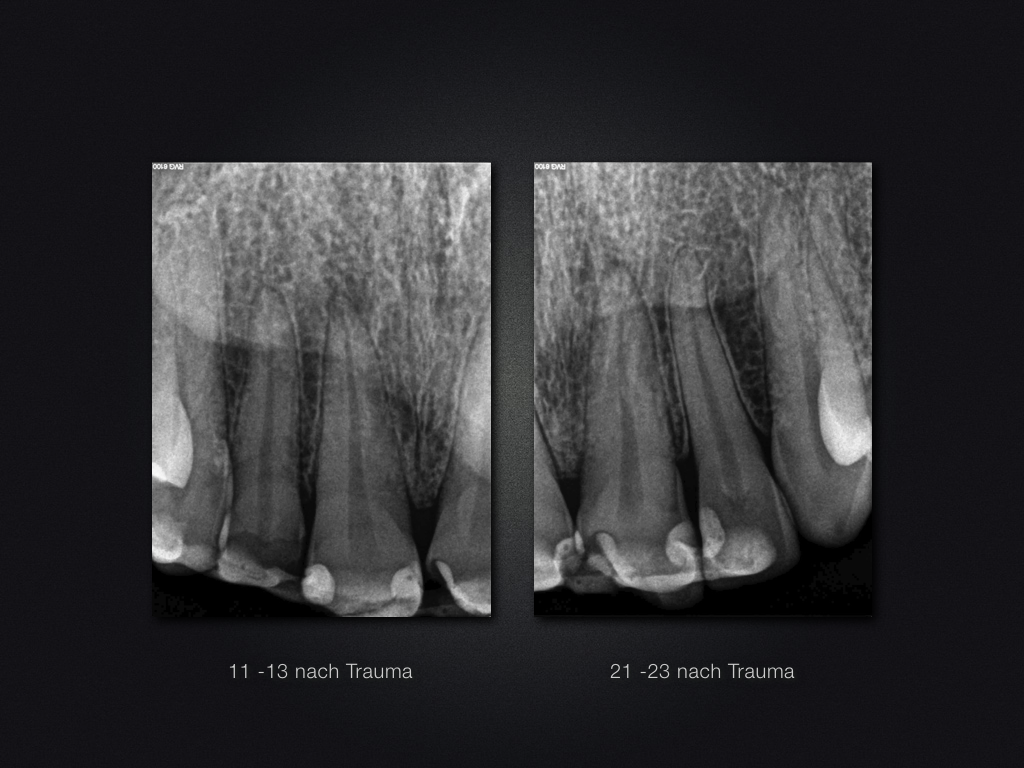

11 21 D Recall.002 Veröffentlicht 22. April 2017 am 1024 × 768 in Traumaspätfolge – knöcherne Ersatzresorption